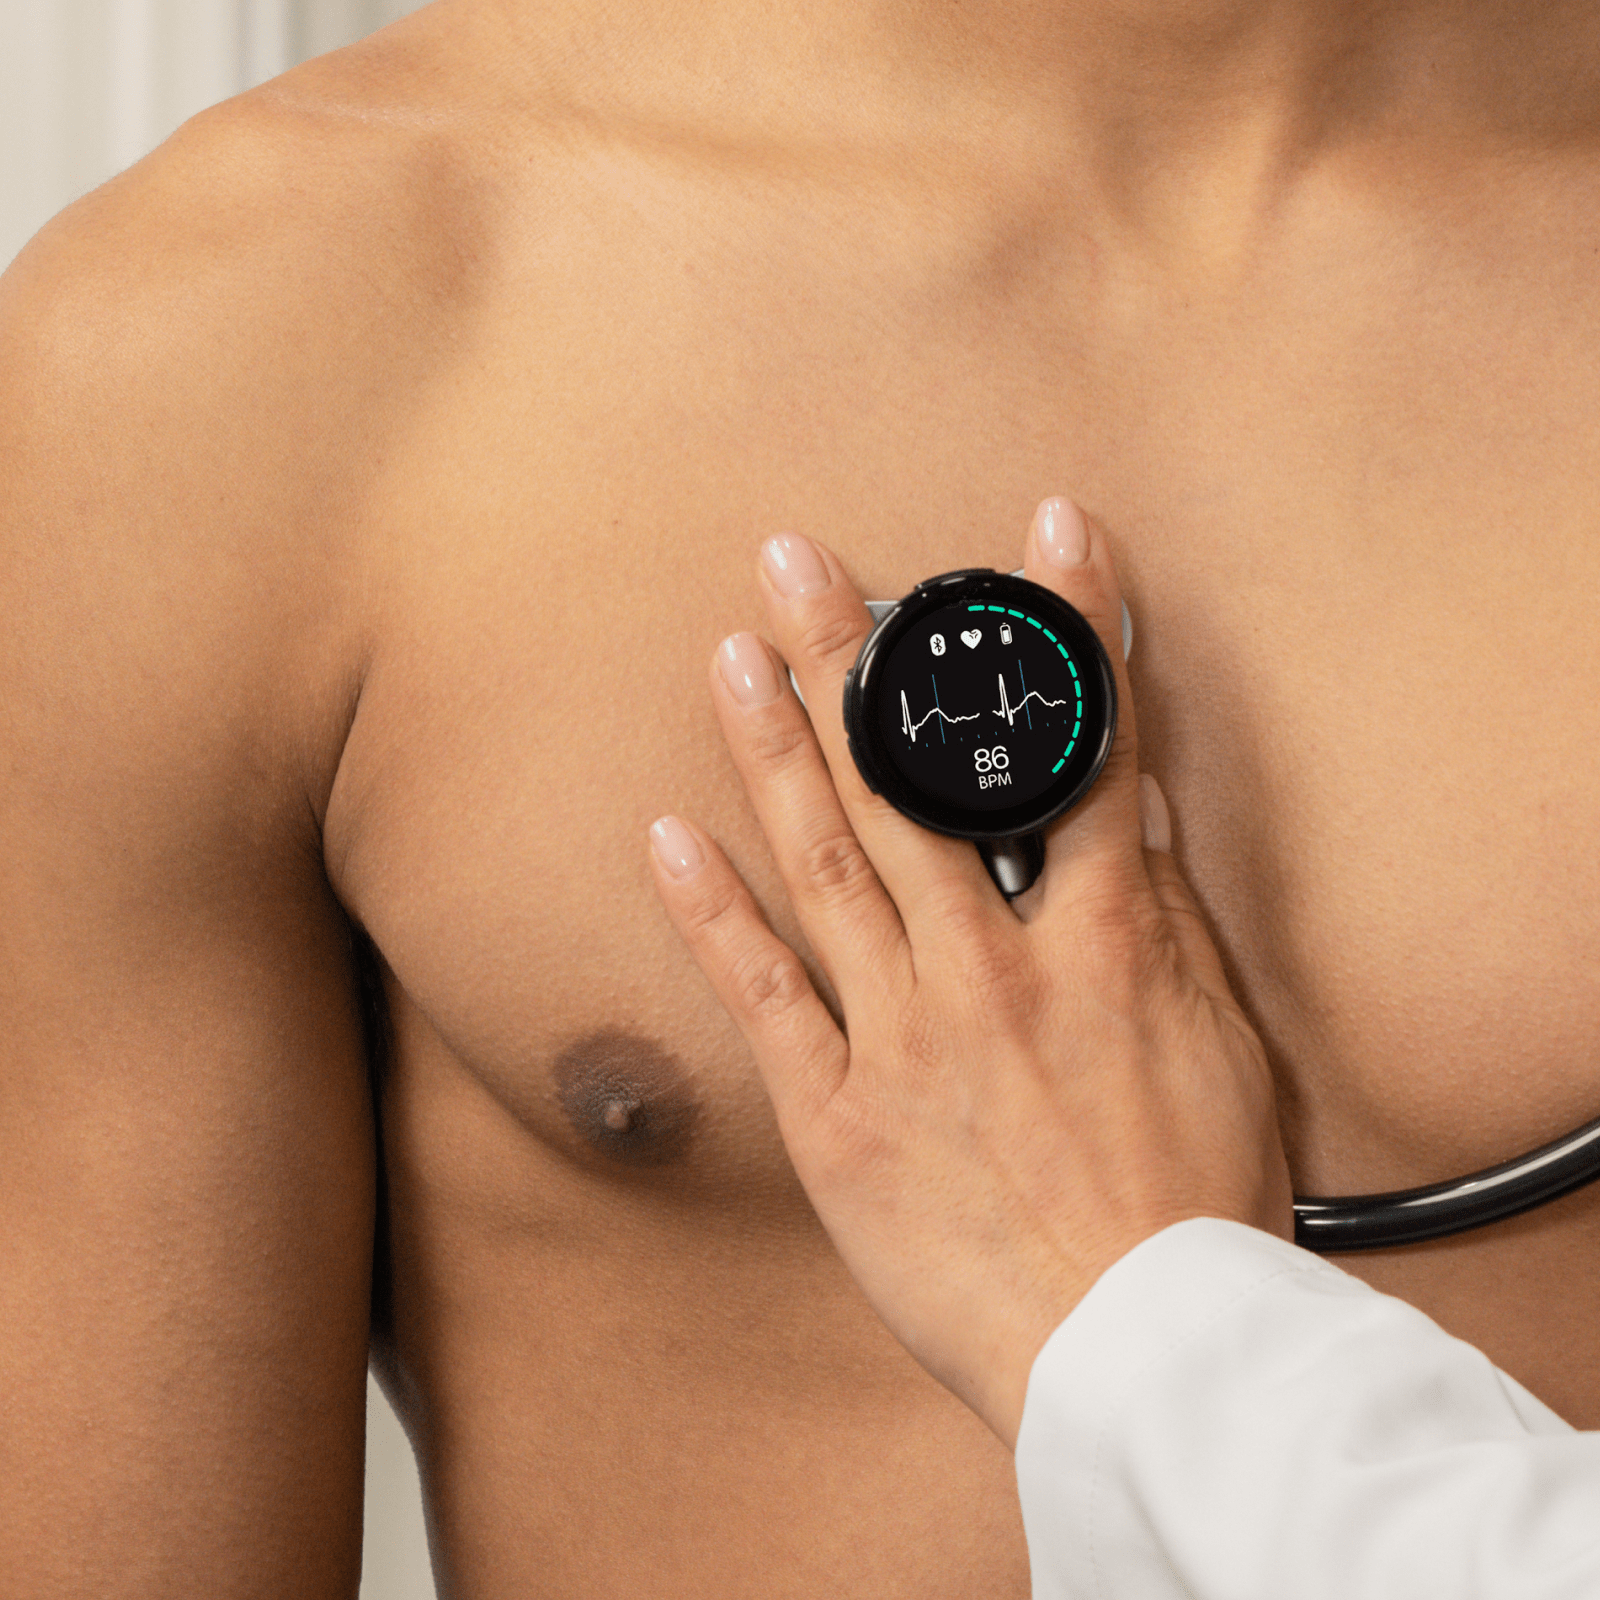

Go beyond sound alone.

For the first time ever, measure heart rate, visualize 3-lead ECG, and see detection results — right on a built-in, full-color display.